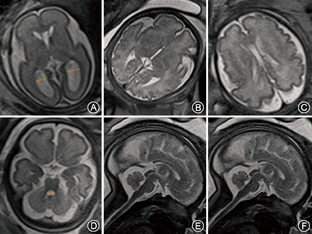

由两名从事胎儿MR诊断工作5年以上的放射科诊断医师单独对MR图像进行评估和分析,选取符合测量标准且两名医师评价结果一致的胎儿进行测量,各脑室及后颅窝池测量平面及方法见图1。测量指标包括:侧脑室三角区宽度(lateral ventricle trigonometric width,LVTW)、第三脑室宽度(third ventricle width,TVW)、第四脑室宽度(fourth ventricle width,FVW)、第四脑室前后径(anterior-posterior diameter of the fourth ventricle,APDFV)、透明隔间腔宽度(cavum septum pellucidum width,CSPW)以及小脑延髓池宽度(cisterna magna width,CMW)。每个指标重复测量3次,取平均值。

中晚孕期各指标随孕周分布及均值变化规律散点图如图2,LLVTW、RLVTW在中孕期均变化不明显,晚孕期早期阶段轻微增长;TVW在整个中晚孕期分布较离散,27周前随孕周增加轻微增长,27周后无特定变化趋势;FVW与APDFV均随孕周增加呈显著线性增长,线性回归方程分别为:y=0.022×孕周-0.043(调整R2=0.642);y=0.018×孕周-0.159(调整R2=0.690);CSPW中孕期随孕周增大缓慢增加,晚孕期的早期阶段相对稳定,随后呈缩小趋势;CMW中孕期随孕周增加轻微增长,晚孕期变化不明显。